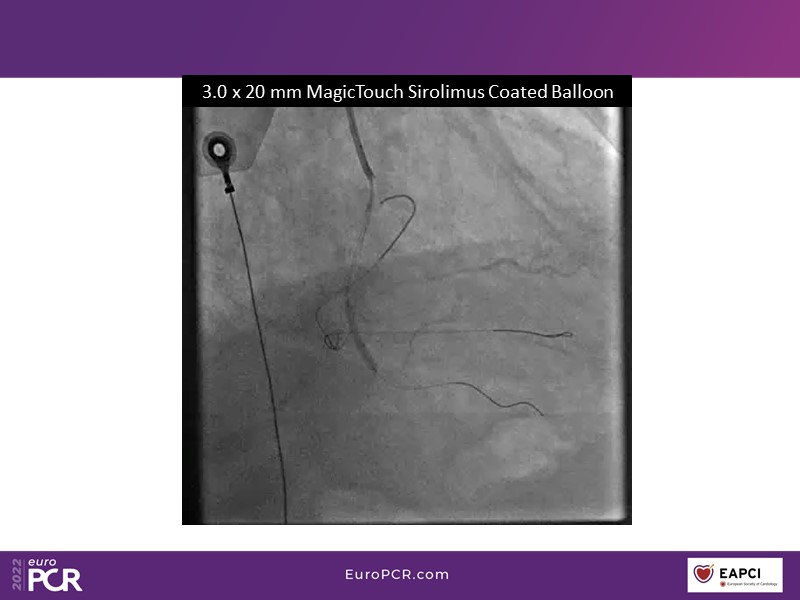

- To find out more about the application and mechanism of a sirolimus coated balloon for coronary artery disease treatment with case presentations in complex settings

- To understand how useful is a DES and DCB stent platform in complex coronary artery disease settings with case demonstrations and follow-up in diabetes mellitus